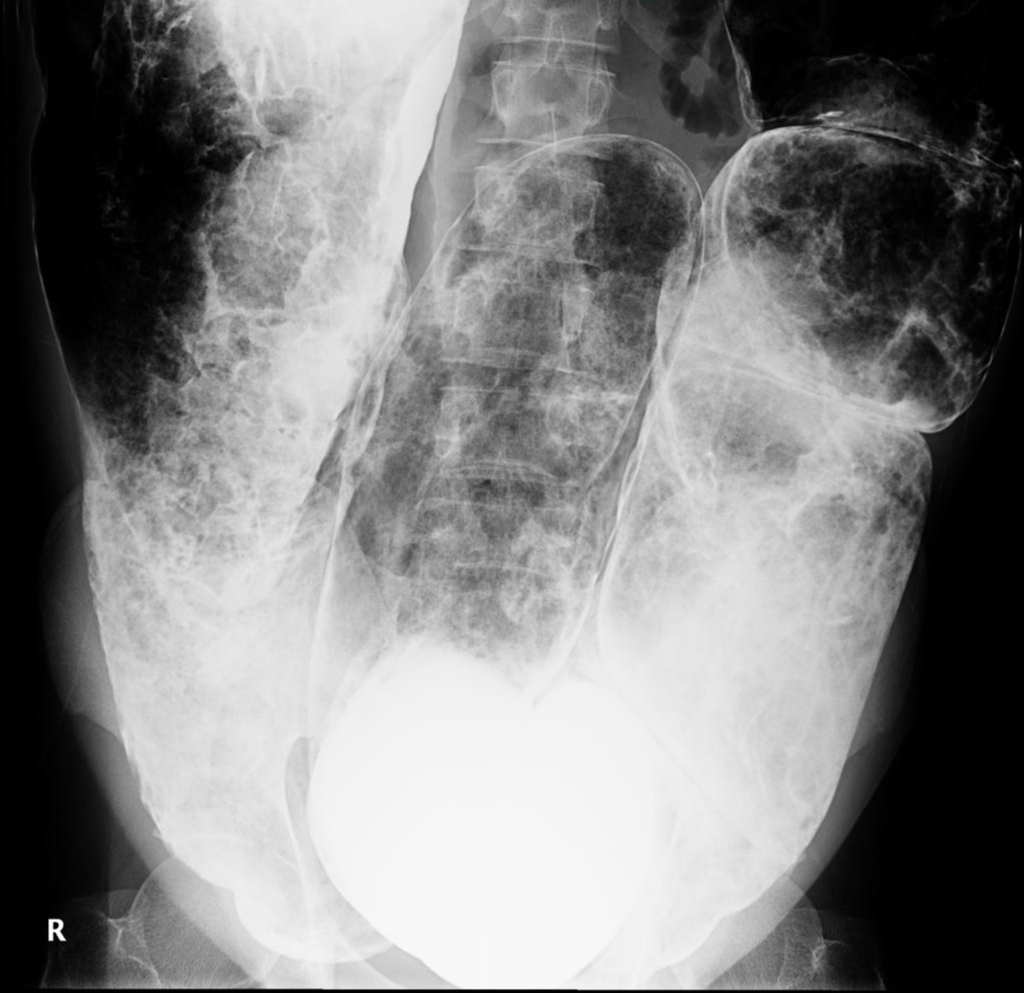

From radiopaedia.org

Ogilvie syndrome Image Ogilvie Bowel In some cases the small bowel may also be involved. A perforated bowel can cause intense abdominal pain, fever, and sepsis, a severe blood infection. Ogilvie Bowel.